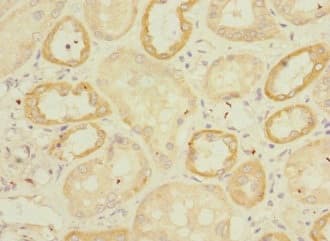

Rabbit Polyclonal Endomucin antibody. Suitable for IHC-P and reacts with Human samples. Cited in 1 publication. Immunogen corresponding to Recombinant Fragment Protein within Human EMCN aa 1-150.

Applications IHC-P